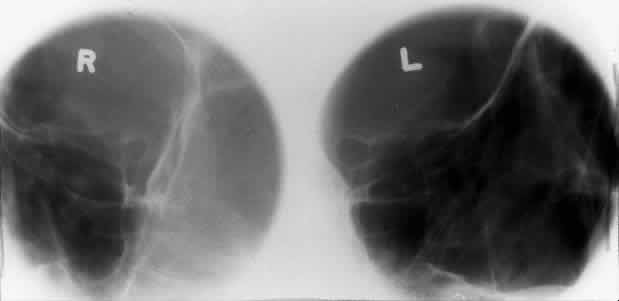

OPTIC FORAMEN (RHESE POSITION)

In 1911 Rhese14 described a projection (Fig. 6) for the evaluation of the ethmoid sinuses and the optic foramen. The patient is positioned with the orbit to be studied against the x-ray cassette. The zygoma, nose, and chin should touch the cassette. The x-ray beam is directed posterior-anteriorly at 40 degrees to the midsagittal plane.5,6 In this position the optic canal is in the inferolateral quadrant of the orbit and oriented perpendicular to the x-ray cassette.15 Variations of this standard position can be used to view other structures of interest. The Rhese projection allows assessment of the orbital apex, in particular, the optic foramen, optic strut, and the upper ethmoid sinus. A pneumatized anterior clinoid process may simulate the optic foramen. The landmark for finding the foramen is to find the planum sphenoidale; the optic foramen lies at its lateral end. The optic canal may be evaluated for expansion or compression by disease processes, such as optic nerve tumors (glioma and meningioma) and trauma. CT and magnetic resonance imaging show much better detail and therefore have replaced the use of plain films for evaluation of the optic canal.

Fig. 6. A and B. Schematic showing positioning for an oblique apical projection (Rhese position). (CR, central ray; CM, canthomeatal line) C. Radiograph of an oblique apical projection. (a, right optic canal; b, optic strut; c, superior orbital fissure; d, ethmoid sinus; e, planum sphenoidale; f, greater wing of sphenoid) (A and B; Rao VM, Gonzalez CF: Plain film radiography and polytomography of the orbit. In Gonzalez CF, Becker MH, Flanagan JC [eds]: Diagnostic Imaging in Ophthalmology, pp 1–7. New York, Springer Verlag, 1986)

The optic foramen should measure 6 mm vertically and 5 mm horizontally. Asymmetry greater than 1 mm or a vertical dimension greater than 6.5 mm is considered abnormal.15,27 Ninety-eight percent of patients have optic canals that vary by less than 1 mm.27 Concentric enlargement of the foramen and optic canal can be seen with optic nerve gliomas, meningiomas, neurofibromatosis, and less commonly an aneurysm of the ophthalmic artery (Fig. 16). A decrease in the optic foramen and canal dimension can be seen in fibrous dysplasia, Paget's disease, hyperostosis secondary to a meningioma, or microphthalmos (Fig. 17, Table 1).

Fig. 16. Oblique apical projections showing the optic foramen. The left optic foramen has concentric enlargement from an optic nerve glioma. The foramen should not have greater than 1 mm of asymmetry.

Fig. 17. Bilateral optic canal compression from fibrous dysplasia. There is diffuse bone thickening in each orbit. Note small size of optic foramen (arrow).